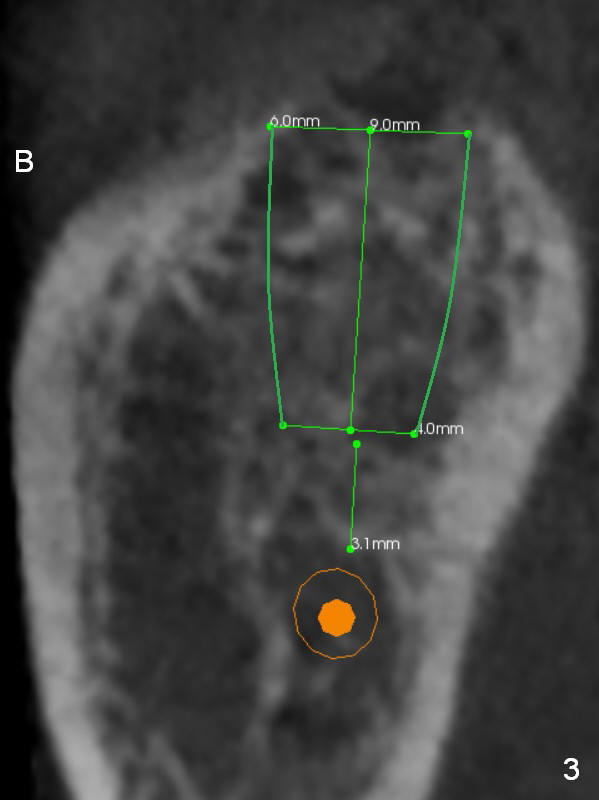

A 65-year-old woman is afraid of dentistry.  After loss of the tooth #18 (Fig.1 with upper RPD), she feels necessary to have an implant (Fig.2).  Since the ridge is wide (Fig.3), a flapless approach is adopted (Magic Split, measure the diameter of its handle).  After 1.6 mm pilot drill (9 mm stopper) and Marking Drill (know the diameter of the large portion), use 4.8 mm Magic Drill (spacer set 2.5 mm, stopper 11 mm).  Try in 5.5x9 mm dummy implant and most likely 6x9 mm definitive one.